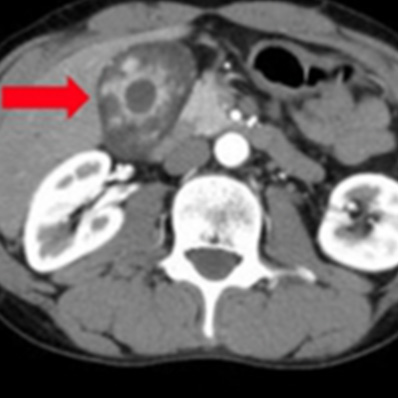

外傷性脾損傷

外傷による腹腔内出血